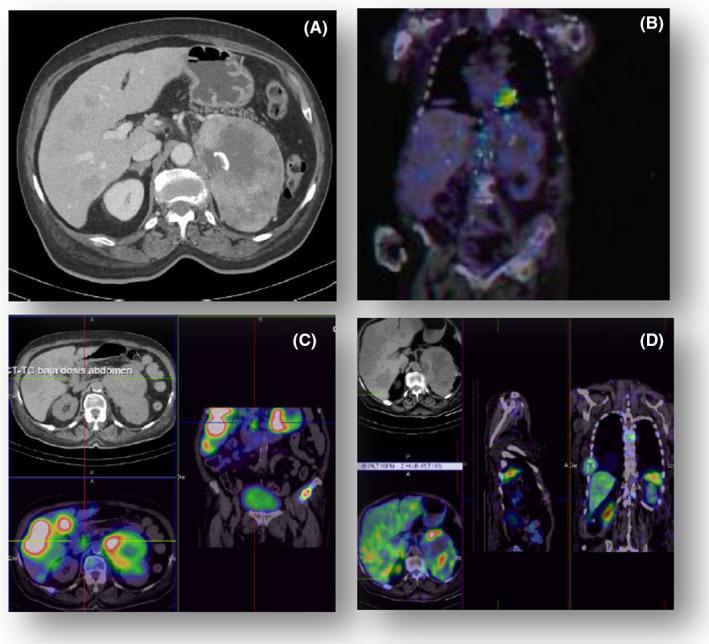

Persistent hypoglycemia due to an IGF-II-secreting malignant pheochromocytoma: a case report and literature review.

A malignant pheochromocytoma with IGF-II-mediated hypoglycemia is reported; although treatment was cumbersome and evolution unfortunate, this diagnosis must be kept in mind when dealing with NICTH's differential diagnosis.